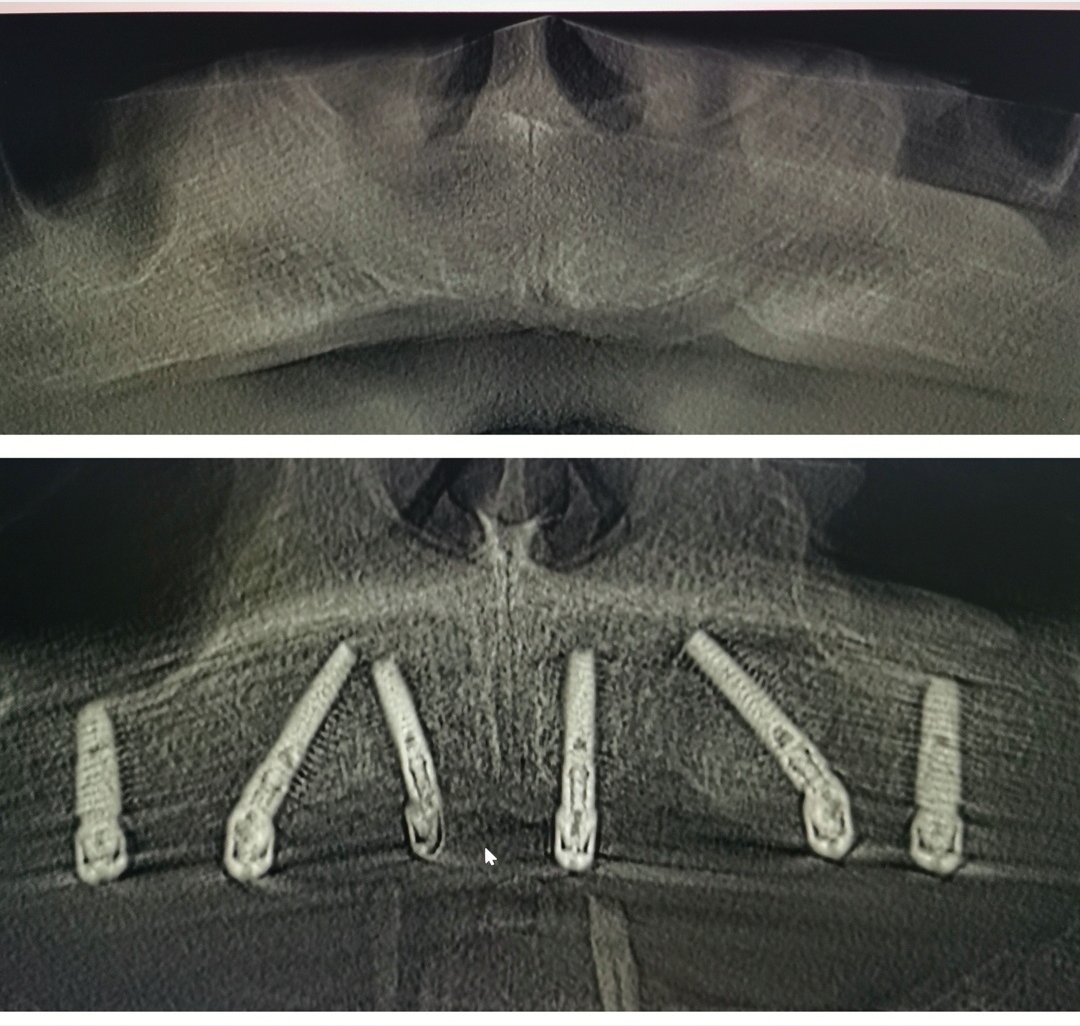

Fotografie